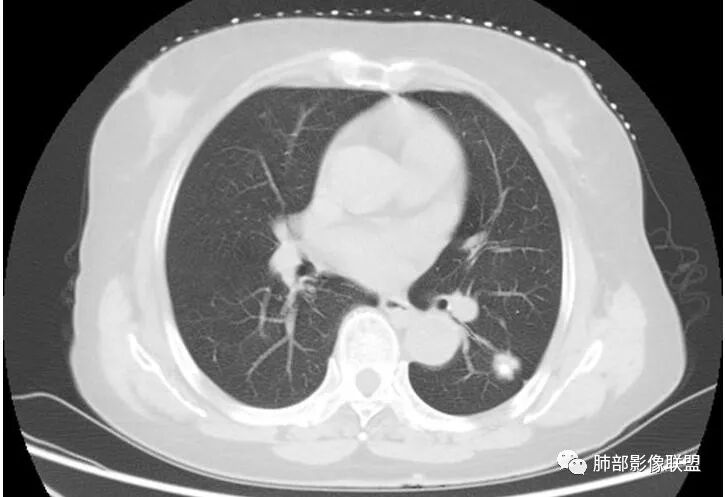

老年女性,气喘入院,发现左肺占位

睡神-阿豆豆:左肺下叶背段占位,边界尚清晰,有深分叶,有胸膜牵拉,有血管集束,支持恶性病变,不支持的如下,短毛刺不明显,病灶内有钙化。结核的话周围没有卫星灶。综合考虑肿瘤,鉴别结核。一切∮随缘:左肺结节,边缘光整,有分叶,轻度牵拉胸膜,形态规则,其内可见小片状钙化,增强后可见强化,病灶内似见小空泡,考虑:隐球菌,鉴别类癌蔡磊:左肺下叶占位,边缘较清,有深分叶,收缩牵拉线边缘光、清晰,内有钙化。与支气管关系不密切,增强后有强化,考虑恶性在前,错构、结核次选。M-Imaging :病灶边缘平直,其内斑片钙化,炎性肉芽肿,PC德芙~云味:左肺下叶占位,边缘较清GGO,有深分叶,边缘有膨隆有平直,胸膜牵拉,内有钙化。支气管近端有阻塞,有血管进入,增强后有强化,考虑恶性,待排隐球。丽:左肺下叶病变,边缘模糊不清,可见深分叶,内粗大钙化,轻度强化,不除外恶性可能飞鹰行动:左肺下叶病灶,有膨胀性表现,可见分叶征象,内部钙化位于一侧,见可疑小泡征,相邻叶间胸膜增厚,增强后可见血管穿入,其血管边缘毛糙,考虑恶性病变,腺癌,鉴别结核。巴伟:首先支持炎性红日东升:左肺下叶结节,边缘较光整、清晰,有分叶,外缘轻度牵拉胸膜,总体形态偏平直收缩,其内可见类圆形规则钙化(面积大于10%),增强轻度强化并见血管显影。考虑良性病变,炎性肉芽肿。平安是福:左肺下叶结节,轻度分叶,病灶内见钙化,血管穿行,中度均匀强化,边缘可见胸膜凹陷及平直,考虑结核,PC,鉴别诊断腺癌。Lotus:炎性可能性大,结核?张小兵:病灶整体以收缩为主,考虑炎性肉芽肿RockJ-ason:考虑炎性病变,鉴别腺癌张延军:左下肺结节,边缘平直,伴局限性凹陷,密度不均,内见钙化结节,良性?结核?病灶下方见穿行增粗的血管影,排除占位紫气东来:良性,结核肉芽肿,万载鑫:考虑感染性病变

深分叶,脐凹征;边缘GGO边界清楚

就这几条就要考虑恶性

南边:你看看这个主体层面,大的一些层面,看看纵隔窗跟肺窗一对比,就发现病变不密实,似乎缩小了一大半,这就不正常了。